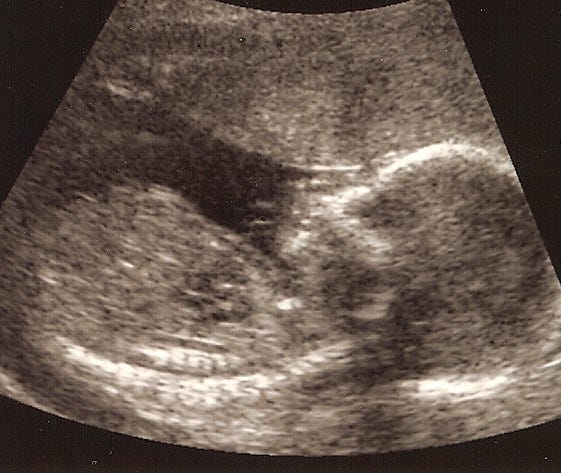

Today I paced in a dark room

and watched on a dark screen

a white line that was the valve

of your ventricle beating

out an irregular rhythm

with extra beats.

Hoosh-hoosh—You were so small

when I saw the flicker

for the first time. You were

within. And I saw your heart

before I saw your face,

the grainy white beat on a dark

screen that made my heart sing.Once I found myself in the cardiologist’s office on Valentines Day with my almost 8-year old son. That boy will be 15 next week. Anyway, this is a love poem to that child, and more specifically to his beating heart. The actual, physical organ, which I don’t think gets quite enough attention in the rush to make it a metaphor.